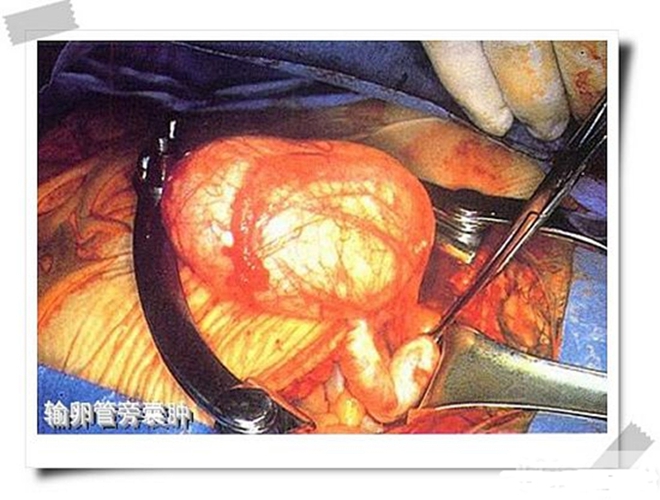

輸卵管巧克力囊腫

輸卵管巧克力囊腫排出

輸卵管囊腫手術